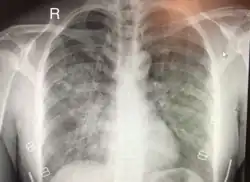

Edema pulmonar de grande altitude

Edema pulmonar de grande altitude é um edema pulmonar que pode ocorrer em sujeitos saudáveis expostos a hipóxia de altitude e não devido a insuficiência cardíaca. Os sintomas podem incluir dificuldades respiratórias (dispneia), tosse, respiração crepitante e dor torácica. Podem também ocorrer alterações de consciência devidas a hipoventilação. Geralmente ocorre acima de 2500 metros de altitude.[1]